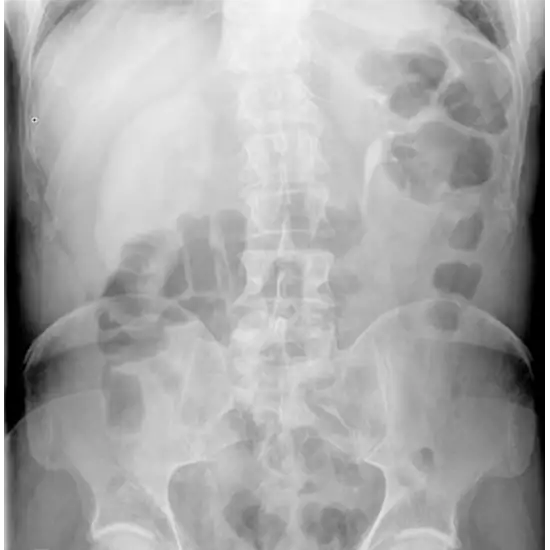

X-Ray Nephrogram

A nephrogram is a diagnostic test performed in X-Ray department. An injectable radioactive substance that can be taken up and secreted by the kidneys is delivered (i.v.). Then a unique camera is put behind the torso, above the kidneys. This camera picks up radioactive drug signals. The test results are the product of computerized processing. The Nephrogram describes the structure and function of the kidneys.